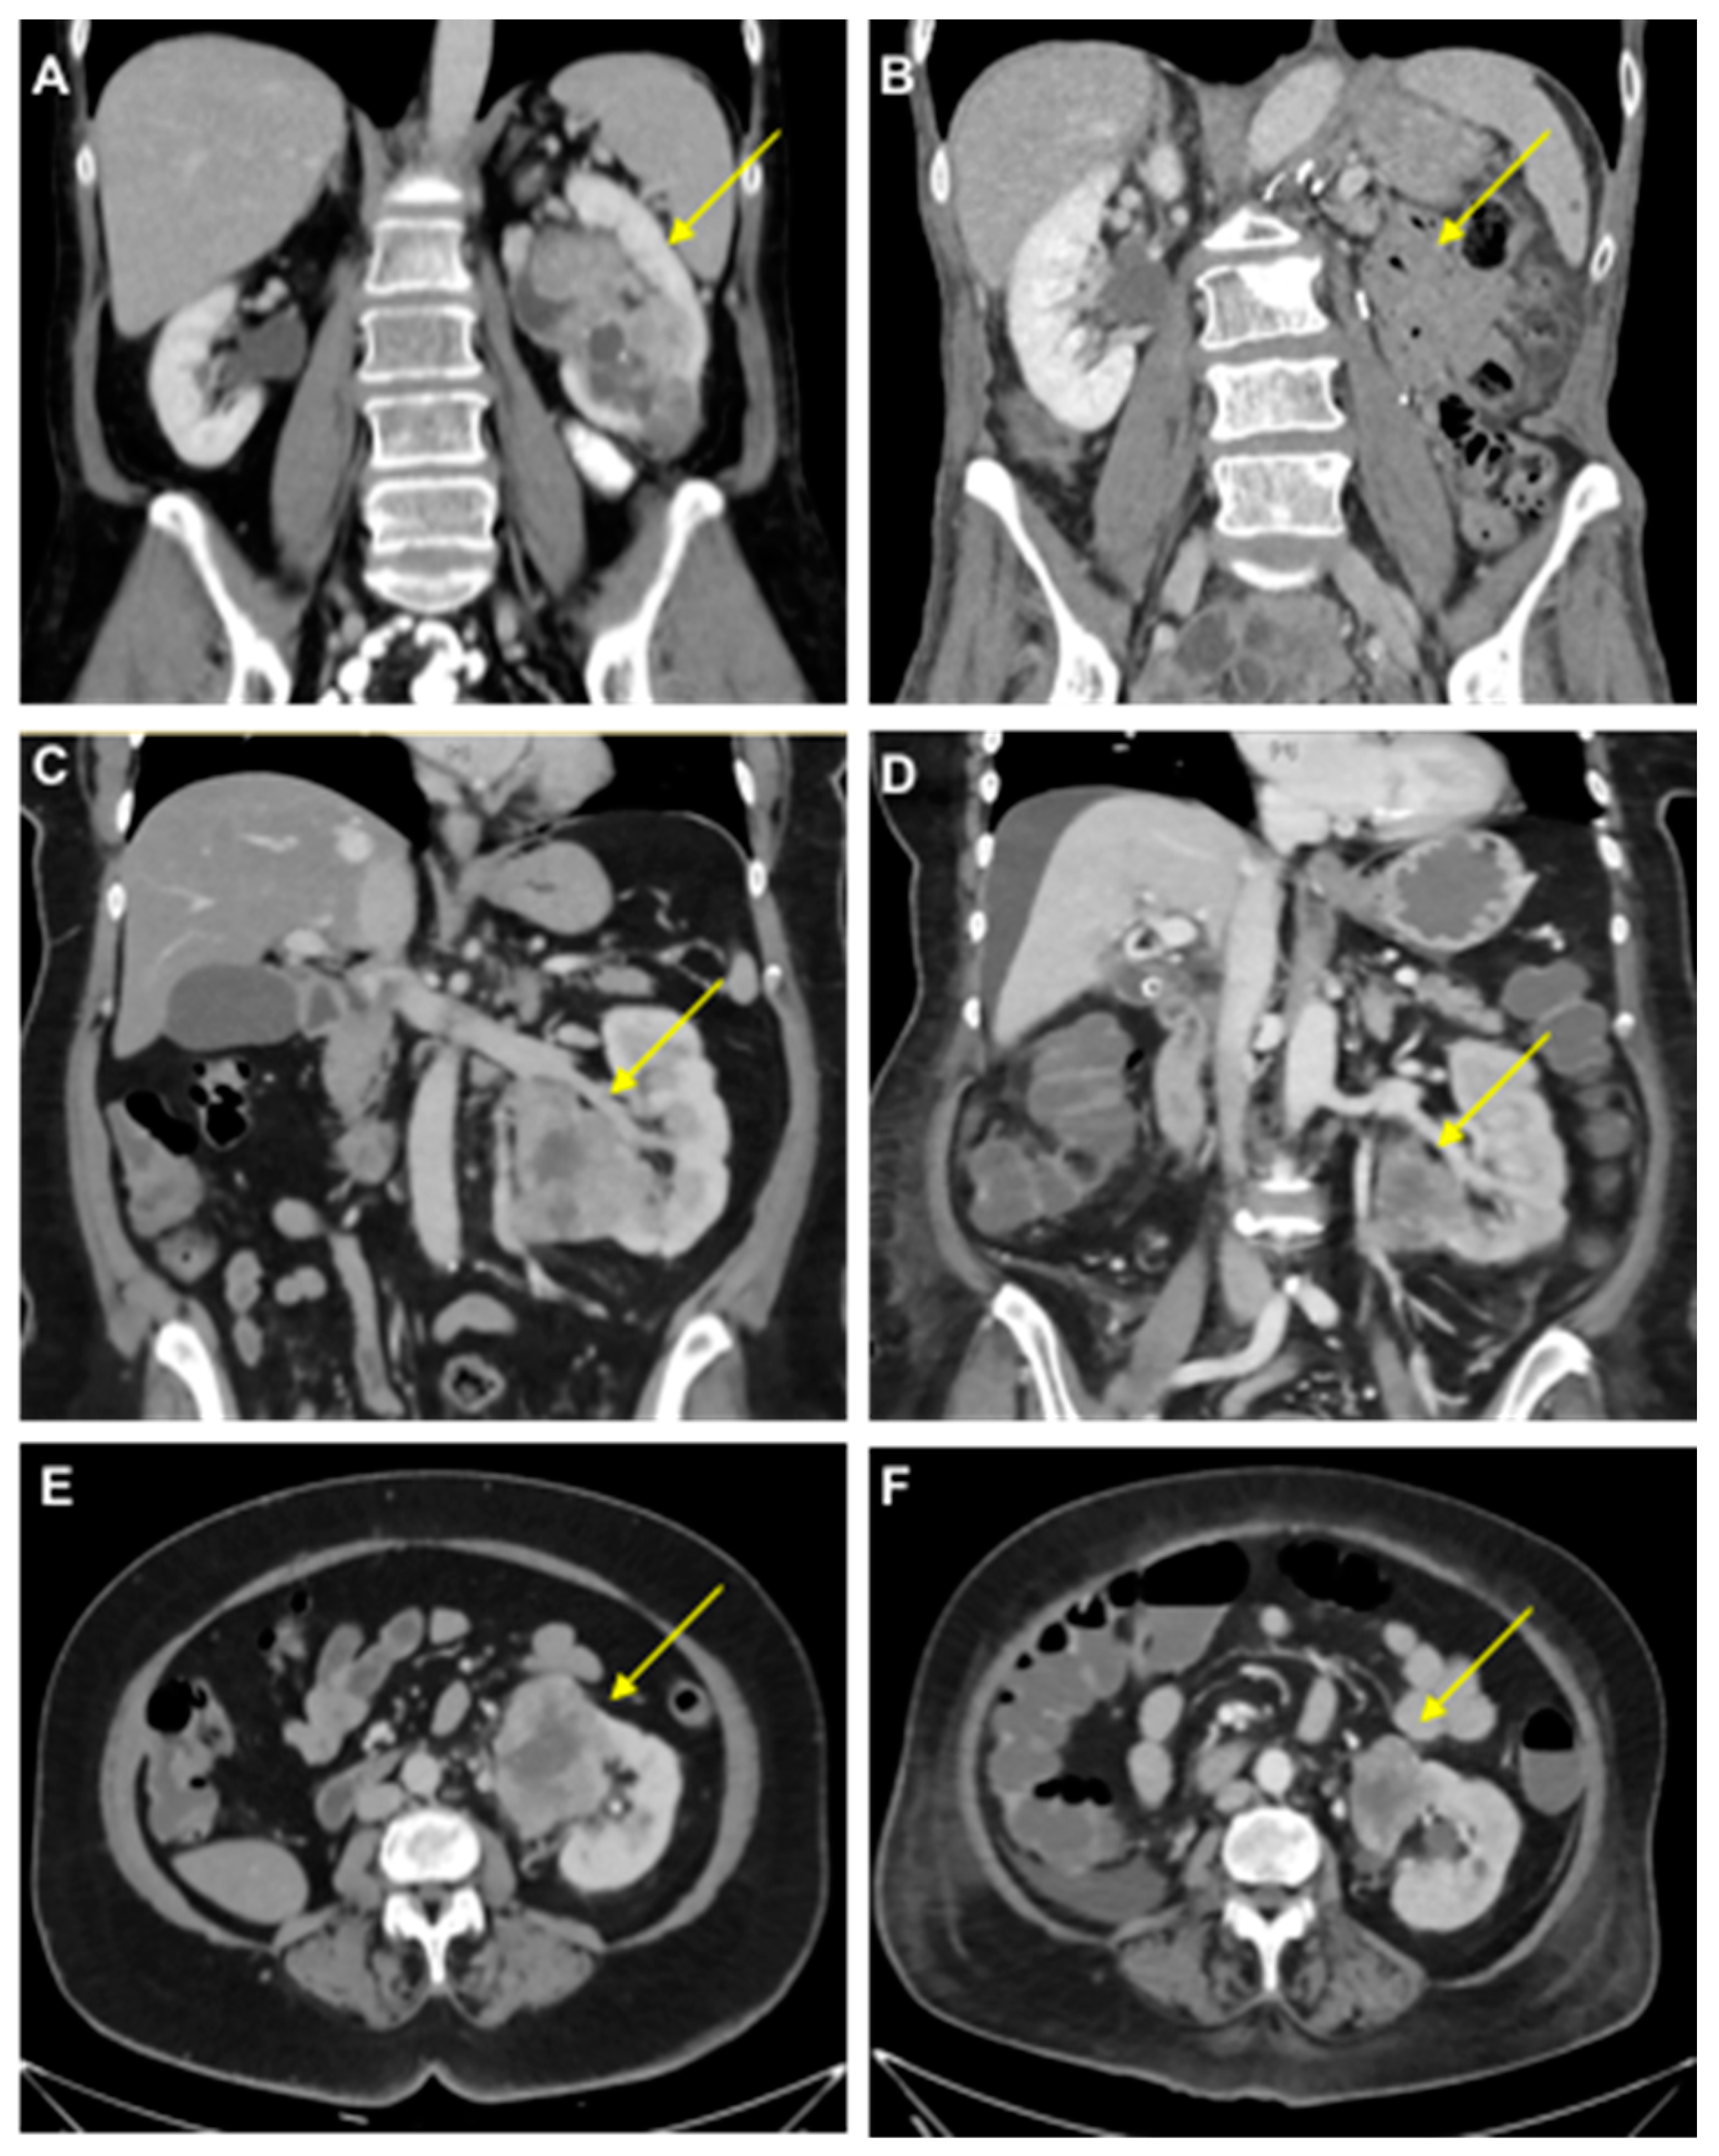

- Case study 3:

- Case study 4: